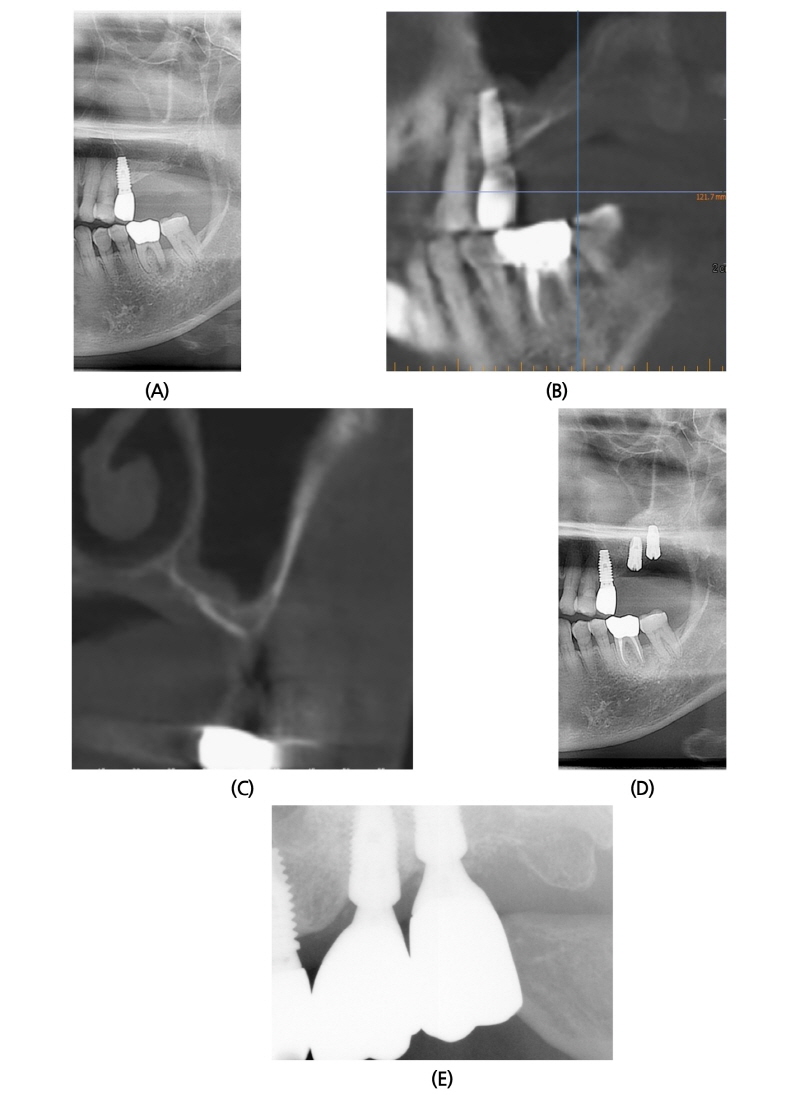

2015년 3월 11일 74세 여성이 앞니가 많이 흔들리고 이 없는 부위에 임플란트를 하고 싶다는 주소로 본과 내원하였다(Fig. 2A). 환자는 고혈압 medication 중이었으며, 4-5년 전부터 L/C 내과에서 골다공증약(Bisphosphonate)을 복용 중이었다. 내원 당시 좌측 상악골 #26 부위에 지름 6 mm 정도의 부골이 노출되어 있었으며, 조직검사 결과 Necrotic bone fragments with candida infection으로 진단되었다. 이에 2015년 4월 3일 좌측 상악골에 대한 부골 절제술을 시행하고, antibiotics medication 처방하였다. 주기적 외래 검사 및 dressing 시행하였으며, 2015년 10월 14일 외래 검사 결과, 임상적으로 #26 부위 complete mucosal covering 되고, 방사선 사진상으로 sinus floor에 bone apposition되는 소견을 보였으며, 2015년 10월 14일 CBCT 소견상, 상악 좌측 무치악 부위는 협측과 치조정 부위로 골함요가 있는 것 이외 특기할 골괴사 소견을 보이지 않았다(Fig. 2B, 2C). 2015년 11월 17일 좌측 상악동 골이식술 및 #26i, 27i 임플란트 동시 식립술을 시행하였다(Fig. 2D). 골이식재로 ICB® 1.25 g과 MBCP® 0.5 g을 혼합하여 사용하였으며, Bone window는 opening하면서 채취한 cortical bone을 다시 덮어주었다. 차단막은 사용하지 않았다. 임플란트는 #26, 27 부위에 Implantium® (Ø4.8 × 10 mm, drilling Ø3.8 mm/ Ø4.8 × 10 mm, drilling Ø3.8 mm) 식립하였다. 술 후 18개월 후에도 임상적, 방사선학적으로 양호한 상태를 보이고 있다(Fig. 2E).